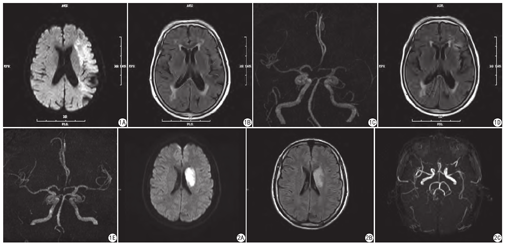

276例AIS患者中,FVH阳性者为149例,其中135例90.60% (135/149)是颈内动脉颅内段和大脑中动脉M1、M2段的狭窄,137例91.95% (137/149)血管狭窄程度呈2、3级(图1),分别显著高于FVH阴性组62.99% (80/127)、35.43% (45/127)(图2)。分析得出血管近端严重狭窄及闭塞更易出现FVH征象,且差异具有统计学意义(P=0.011,P=0.000)(表1)。FVH的出现与Willis环分型差异无统计学意义(P=0.631)(表1)。

FVH阳性组血管狭窄程度3级的患者共81例,59例患者复查资料不完整,无FLAIR或MRA序列,故共分析随访患者22例。血管再通组11例,其中9例FVH消失(9/11,81.82 %),未再通组11例FVH均未消失(11/11,100.00%),差异具有统计学意义(P=0.000)。

22例患者中,预后良好组13例,预后不良组9例,两组间基线FVH级别及治疗后血管再通差异无统计学意义(P=0.290,P=0.080),基线NIHSS评分和治疗后FVH消失情况差异具有统计学意义(P=0.000,P=0.002) (表4)。